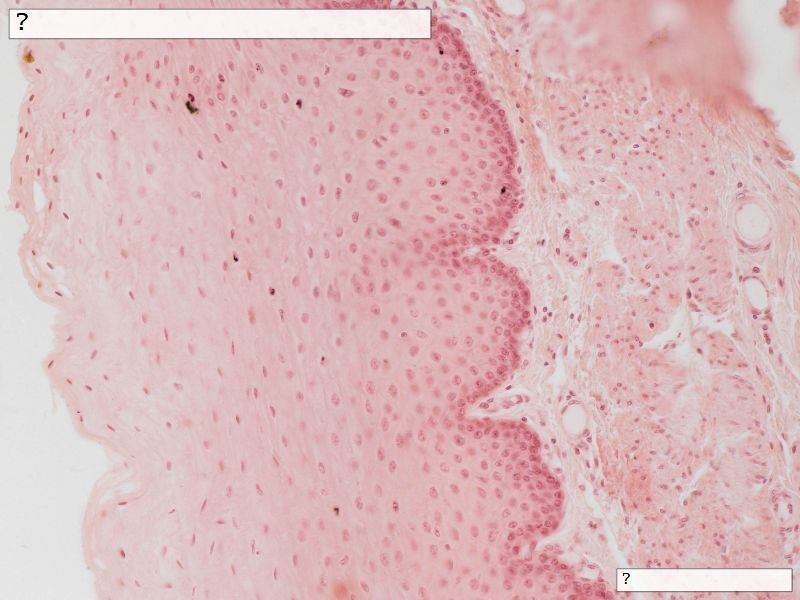

Fill in all the missing labels, and assess as you move through the slides. Answers on the down slide. It is important to do this using pen and paper, and not just glance through the images.